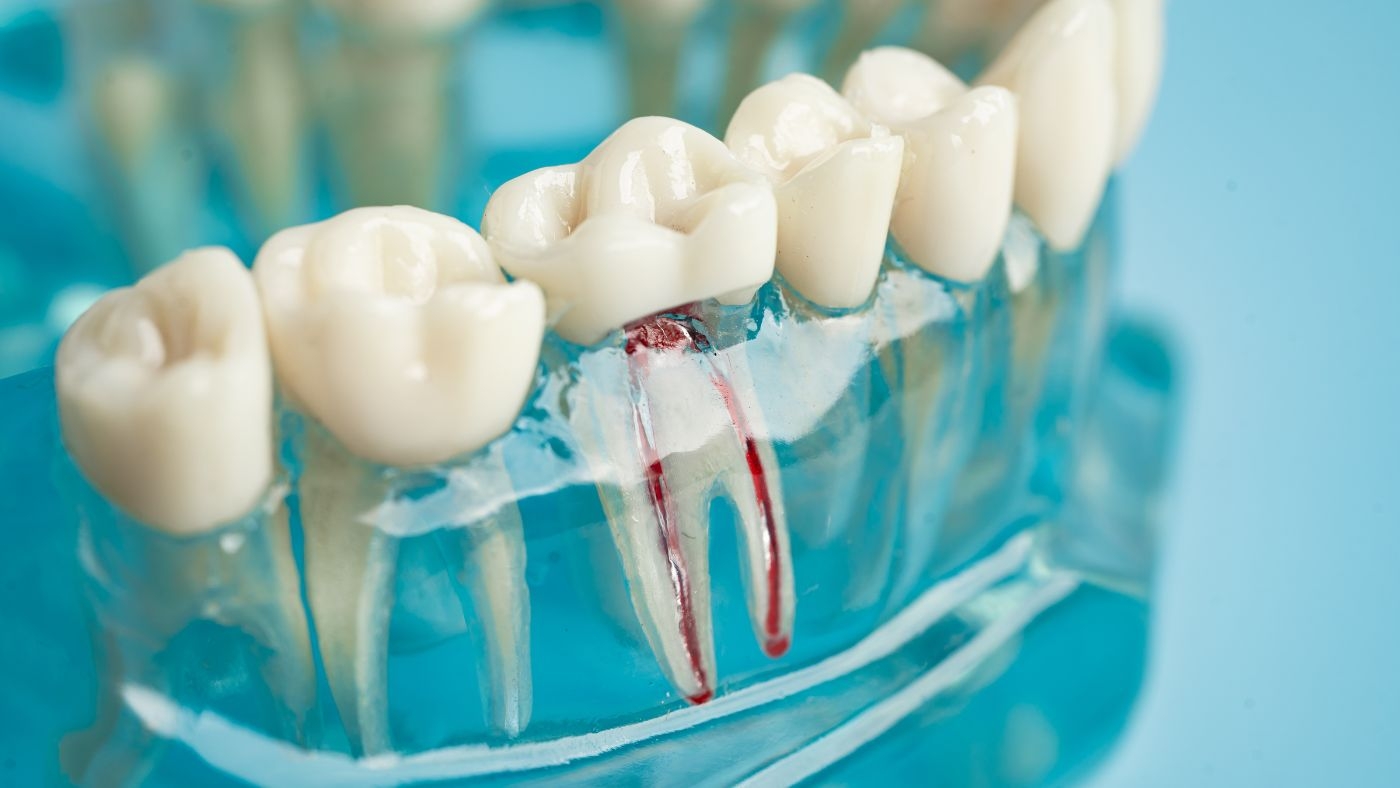

根幹治療とは、歯の内部にある神経や血管が通る根幹という部分の治療を指します。

虫歯が進行して根幹まで細菌が達した場合、根幹治療が必要になります。

根幹治療の流れは、まず歯科医師が根幹内部の感染した組織を除去します。

その後、根幹内部を消毒し、清潔な状態を保つための治療を行います。

根幹治療では、根幹の形を整えながら、細菌を徹底的に取り除くことが重要です。

根幹内部が完全に清潔になったら、根幹充填という処置を行います。

根幹充填後は、歯の上部を修復する治療へと進みます。